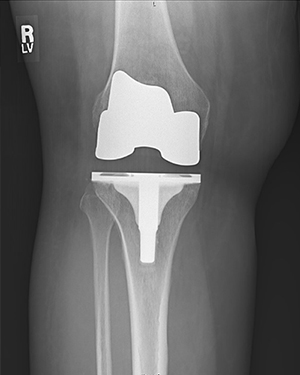

Revision Knee Joint Replacement- Two Weeks after Surgery

Ms. D. Z, is 2 weeks from Right knee replacement and 2 months from Left knee replacement.

This is Ms. D. Z, she is 2 weeks from Right knee replacement and 2 months from Left knee replacement. She is walking well with just a cane at 2 weeks post op.